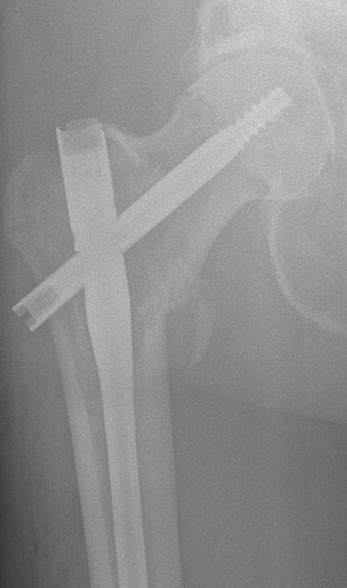

leg top

The rod within the femur and the pin connecting it to the pelvis